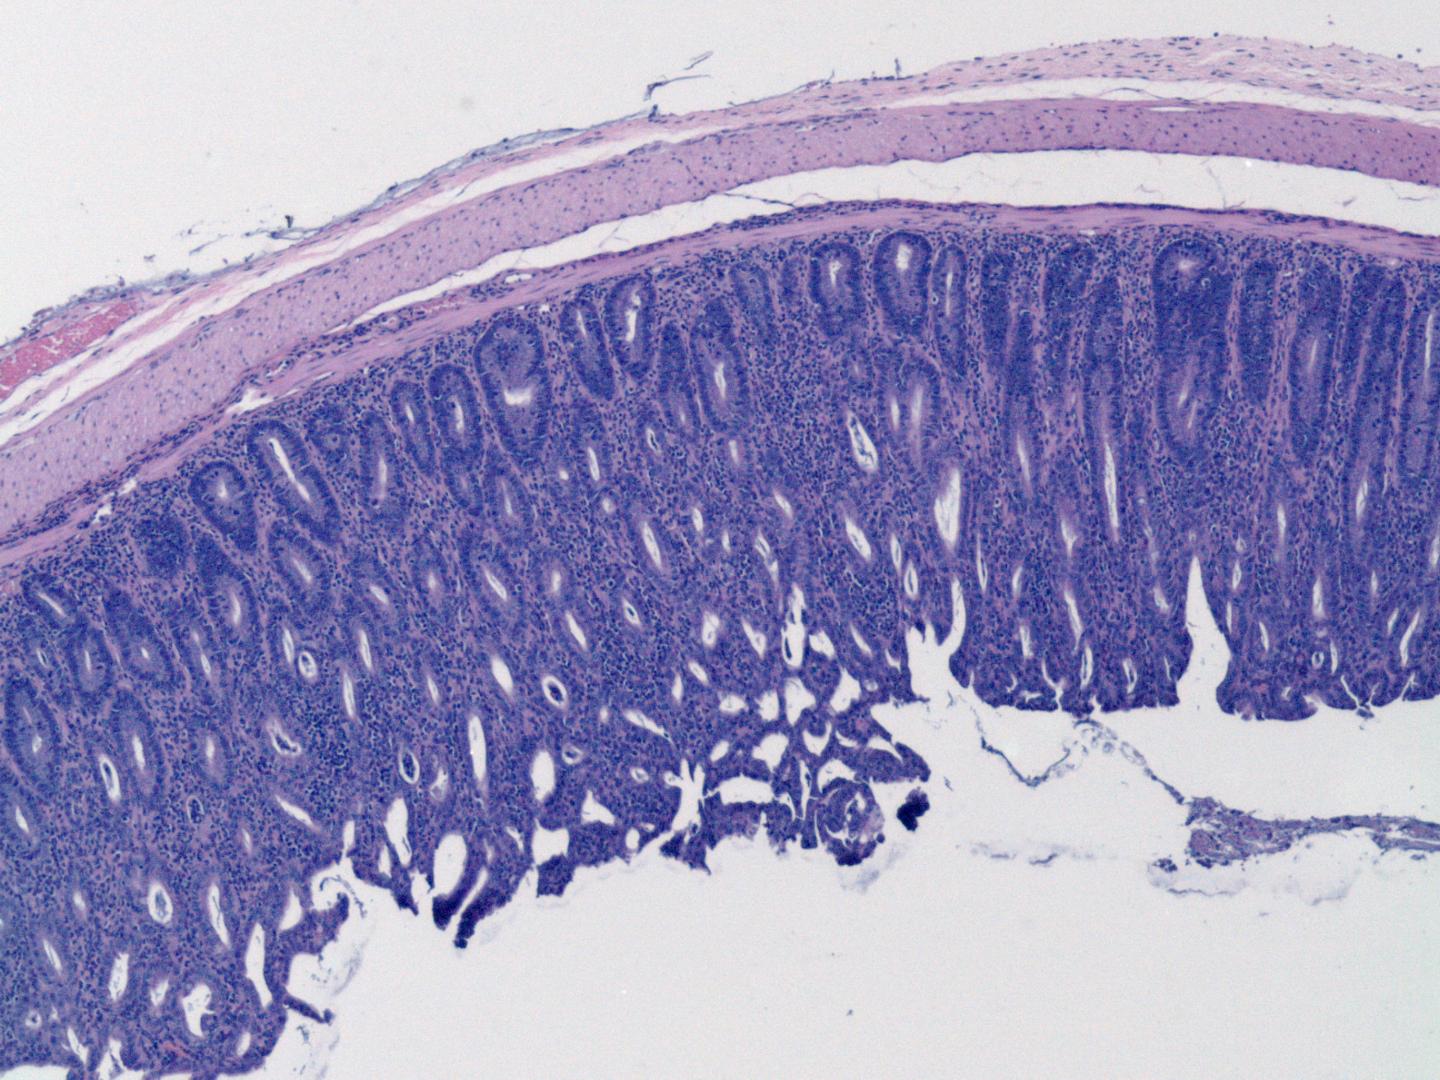

Regulatory T cells are responsible for reining in the activity of other cells in the immune system. They prevent the immune system from attacking the body's own tissues, and tell the immune response to fade when it is no longer needed, acting like an all-clear signal. Underactive regulatory T cells are associated with autoimmune diseases where the immune system attacks the body, including rheumatoid arthritis, multiple sclerosis, inflammatory bowel disease and lupus. Some cancers, on the other hand, have higher-than-usual regulatory T cell activity, preventing the immune system from attacking a tumor and allowing its growth.

In mice with cancer, treatment with the weakened immune cells without Brd9 enabled other immune cells--the fighters and soldiers of the immune system--normally blocked by the regulatory T cells to infiltrate the tumors and shrink them. In mice with inflammatory bowel disease, however, the weakened regulatory T cells left the immune system attacking the digestive tract unchecked. These results suggest that controlling the strength of regulatory T cells has potential for treating both cancer and autoimmune diseases.